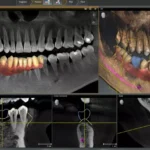

İki tanesi alt çenede ve iki tanesi üst çenede olmak üzere toplam dört adet olan yirmilik dişler, kimi zaman tam olarak diş eti yüzeyine çıkamayabilir. Bu durumdaki dişler, gömülü diş olarak adlandırılır. Tamamı diş eti mukozasının altında kalan dişler olabileceği gibi bir kısmı yüzeye çıkmayı başaran yirmilik dişler de vardır. Bu durumda yapılacak dental görüntüleme ile dişin konumu, kök yapısı incelenir. Yapılacak inceleme neticesinde diğer dişlere zarar verdiği tespit edilen, estetik açıdan problemlere yol açan ve hastayı rahatsız eden gömülü dişlerin çekilmesine karar verilir.